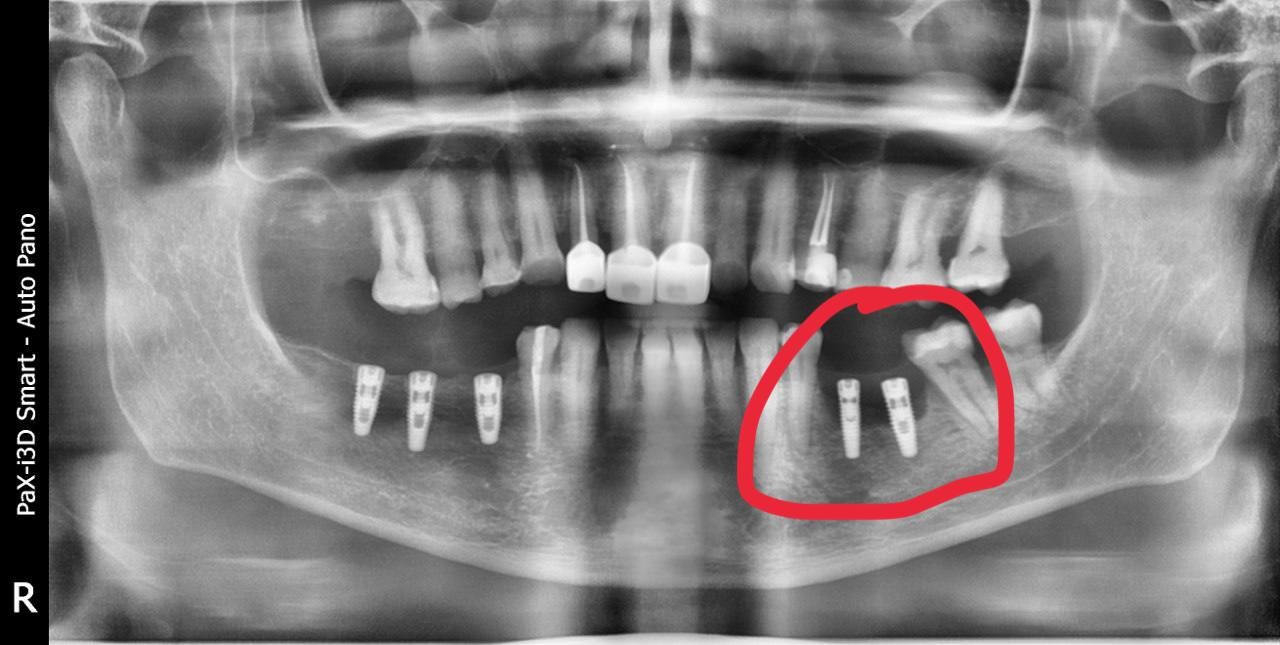

Рентген до/после тотального протезированияЧитать полностью »